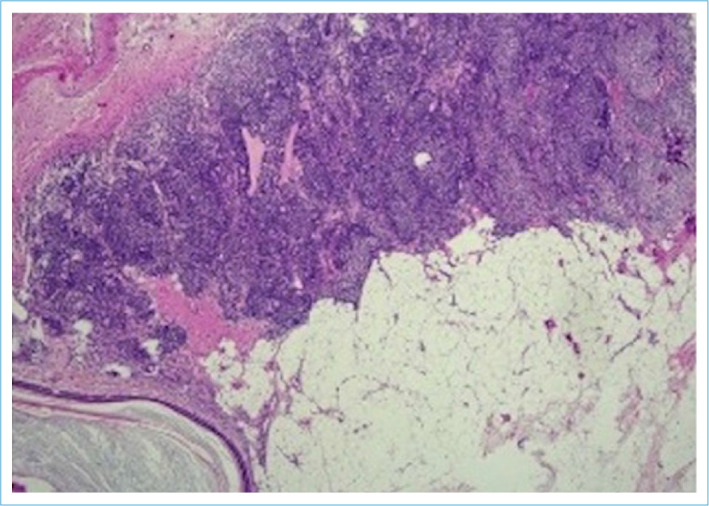

This is a case report of a 19-year-old nulligravid patient with a choroid plexus papilloma tumor in a mature cystic teratoma in the right adnexal area. The patient, who had abdominal pain and dyspepsia, showed a 9 cm diameter mass with a solid/cystic component, initially interpreted as a dermoid cyst in the right adnexal region. Mature cystic teratoma is a benign germ cell tumor and is common in women during the reproductive period. However, choroid plexus papilloma is a rare brain tumor. The diagnosis of ovarian choroid plexus papilloma can be made with imaging tests such as magnetic resonance imaging or computed tomography, and treatment is usually by surgical removal. Only four cases of ovarian teratoma with choroid plexus papilloma have been informed in the English literature, and this issue is the fifth.